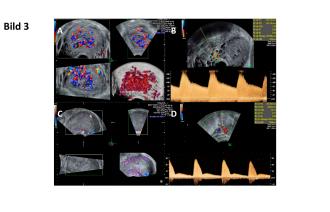

Postinterventionell lassen sich sonographisch deutlich langsamere Flussraten feststellen. Auch das Aneurysma zeigt sich etwas grössenregredient (Abb. 3A und B). Dieser Trend hält an und als Hinweis der progressiven Reduktion des entsprechenden Gefässbettes nimmt die Pulsatilität in der Aa. uterinae stetig zu (Abb. 3C und D).

Eine Woche später ist dieses thrombosiert. Sechs Wochen nach Embolisation lässt sich keine Mehrdurchblutung im Myometrium mehr nachweisen und auch das Aneurysma lässt sich nur noch erahnen (Abb. 4).